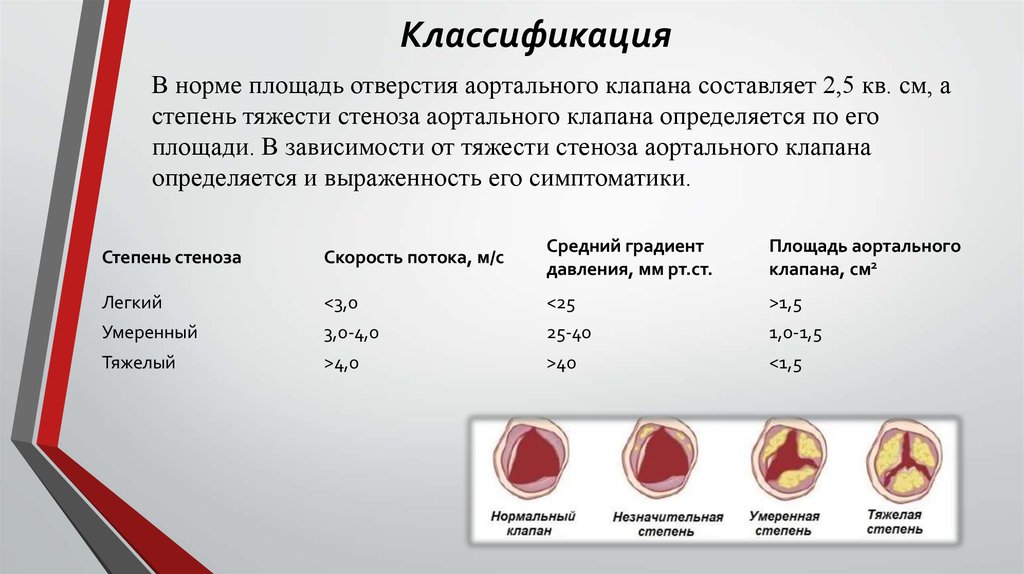

Нормальный диаметр корня аорты: медицинские нормы и отклонения